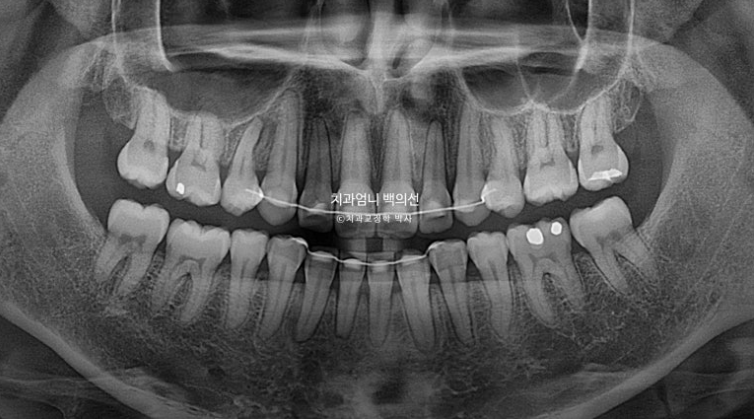

25.06

치근흡수는 없고 치근평행도는 좋습니다.,